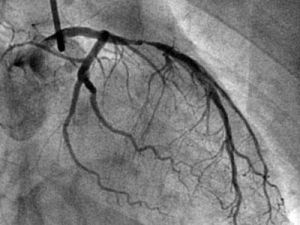

冠狀動脈造影是診斷冠心病的一種有效方法。將導管經大腿股動脈或其它周圍動脈插入,送至升主動脈,然後探尋左或右冠狀動脈口插入,注入造影劑,使冠狀動脈顯影。能較明確地揭示冠狀動脈的解剖畸形及其阻塞性病變的位置、程度與範圍。冠狀動脈造影是目前唯一能直接觀察冠狀動脈形態的論斷方法,醫學界號稱其為“金標準”。冠狀動脈造影術的死亡率約在0.11%-0.14%,心肌梗死率約在0%-0.06%;左冠狀動脈主幹病變患者的心肌梗死與死亡率均約在3.0%。

冠狀動脈造影是一種非常安全、有效的檢查手段。無須開刀,在局部麻醉下僅將特殊的導管經大腿股動脈或上肢橈動脈穿刺後插至冠狀動脈開口,選擇性地將造影劑注入冠狀動脈,記錄顯影的過程。檢查一般只需要15~30分鐘,術後病人平躺12~24小時後就可下地活動,不受年齡、性別限制,絕大部分病人都能接受。現已逐漸成為一項較常規的檢查手段。